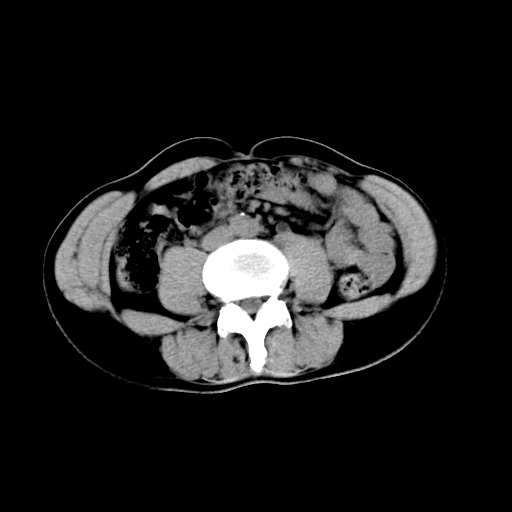

男,47岁,左输尿管结石碎石治疗后10余日。彩超示:左输尿管下段狭窄、输尿管积水。请各位讨论一下左输尿管下段结石还是静脉石?

象是第二狭窄处结石伴以上输尿管、肾盂轻度积水。

输尿管结石伴以上输尿管、肾盂轻度积水。

两侧髂总动脉壁斑状及点状钙化.左侧输尿管行经与左髂总动脉相交后见高密度影,且下段输尿管管腔未见扩张,应该要考虑结石伴以上输尿管及肾盂积水.但右侧结节状高密度影,也应该是结石吧!那以上输尿管未见扩张呢!因此静脉结石可能性也较大.请问楼主碎石前左侧输尿管结石位置.

虽左侧有轻度肾盂积水但不支持结石。1结石边周应该有软组织包绕呈晕征。2钙化点前面见输尿管影也不支持是结石。3彩超没提结石。建议超生复查。

输尿管先位于腹部,后进入盆腔,最后斜穿膀胱壁开口于膀胱,因此,临床上常将输尿管分为腹段、盆段和壁内段。第1个狭窄:在肾盂与输尿管移行处。第2个狭窄:在跨过髂血管处。第3个狭窄:在穿过膀胱壁处。这些狭窄是结石容易滞留的部位。

左侧输尿管有轻度扩张伴有肾盂积水,输尿管下段周围的高密度影不象在输尿管内。

同意,不支持结石。(因显示该高密度影前见扩张输尿管影,另外两侧对称显示)。

左侧高密度影在左侧输尿管的内侧方,所以不考虑输尿管结石.

我认为不是结石的可能性大,因为他的位置和血管钙化的位置邻近